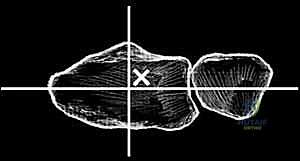

4. إزالة العظام والغضاريف التالفة

باستخدام أدوات جراحية متخصصة، يتم إزالة الصف الأول من عظام الرسغ التالفة، بالإضافة إلى إزالة أطراف عظمة الكعبرة المتآكلة، لتهيئة المساحة لاستقبال المفصل الصناعي الجديد.

قبل تثبيت المفصل النهائي، يقوم الدكتور هطيف بوضع مفصل تجريبي للتأكد من المقاس الدقيق، واختبار نطاق الحركة، والتأكد من استقرار المفصل وتوازن الأربطة المحيطة به.